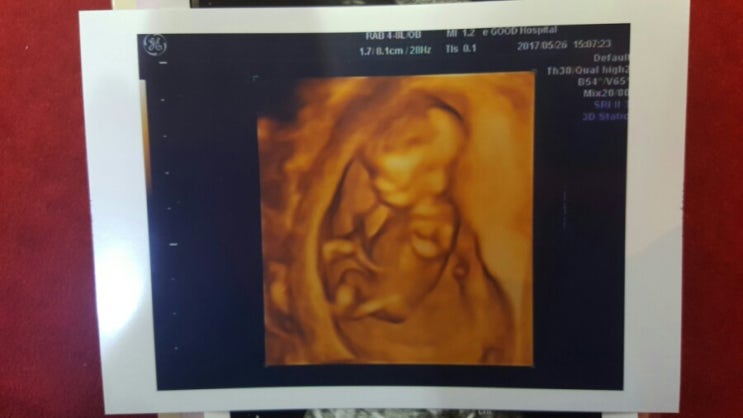

임신12주 / 12주 입덧 토덧 양치덧 다한다 / 목투명대둘레 / 1차기형아검사 / 그네의자

2017.05.26.(임신12주) 8주차에 갔다가 4주만에 다시 간 병원~~ 한달 동안 계속 토하고 울렁거리고 속 쓰리...